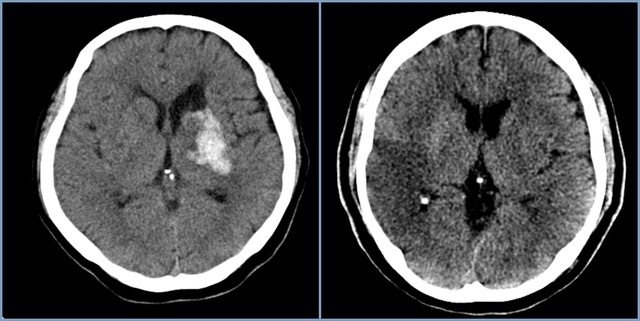

뇌경색은 뇌의 혈관이 막혀서 뇌에 산소와 영양분이 공급되지 않게 되는 상태를 의미합니다. 이런 혈액 공급이 차단되면 뇌세포가 손상되거나 사멸하게 됩니다. 급성 뇌경색은 시간이 지남에 따라 위험성이 증가하므로, 초기 증상을 빠르게 인식하는 것이 필요합니다. 뇌경색은 주로 고혈압, 고지혈증, 당뇨병 등의 만성 질환과 연관이 있습니다.